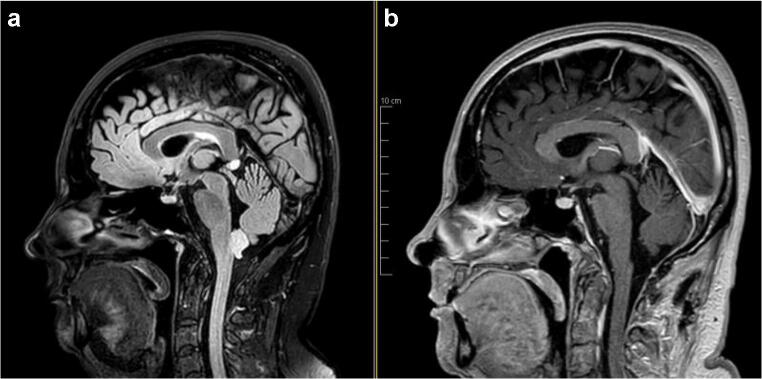

Careful soft tissue closure was achieved using a running Monocryl® 3-0 in the muscle fascia and subcutaneous planes and a running Prolene® 4-0 for the skin closure. The postoperative MRI showed no residual tumor, with minimal stigma of the surgery (Fig. 4). The postoperative histo-pathology confirmed the diagnosis of WHO grade I sub-ependymoma.

Fig. 4.

Pre- and postoperative Magnetic Resonance Imaging (a T2 flair; b T1 gadolinium), showing the complete resection of the lesion